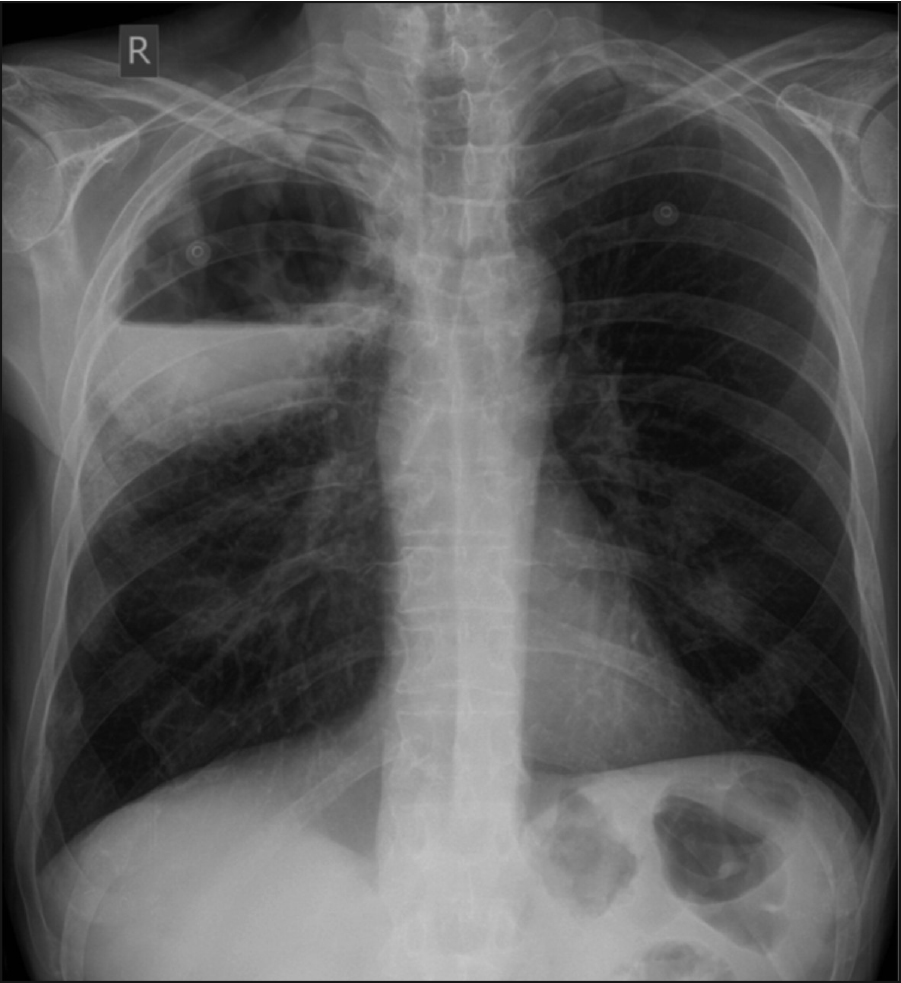

Figure 1. Chest x-ray showing a large cavitating lesion in the right upper lobe

The bedside urinalysis was clear and the ECG was showing a sinus rhythm. His blood tests were predominantly unremarkable with the exception of a C reactive protein of 117 (<10mg/l) and mildly deranged liver function tests. The total white cell count (WCC) was 9 (4-10x109/l). Quantiferon, ACE, ANCA were negative. The chest x-ray showed what appeared to be a large cavitating lesion in the right upper lobe with an air/fluid level (see Figure 1).

A CT chest with contrast was performed which showed a 13x10x12cm cavitating lesion with a large air/fluid level predominantly in the right upper lobe (see Figure 2). Associated with it, there was prominent reactive adenopathy in the superior, anterior mediastinum, as well as in the subcarinal position (see Figure 2).